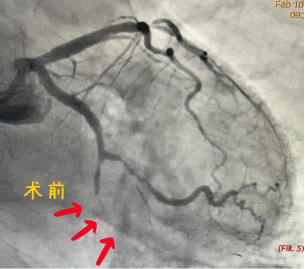

齐峰主任听闻老人家生病以前耳聪目明,平常生活能自理,年前1个月发生了急性心肌梗死,外院就诊,考虑患者年龄大,拒绝为其手术,一直给予药物保守治疗,经过一个月双联抗血小板药物治疗,患者也未出现各种出血并发症,这次生病之后,稍微活动就有心绞痛症状发作,结合患者病史及外院的检查结果,决定为其行PCI手术,开通他的“生命之路”,术中尽量无植入,避免术后出现出血等并发症。老爷爷住进云南阜外医院冠心病一病区,温馨的病房,干净整洁的病床,关爱有加的医护团队,给爷爷制定了周全的诊疗计划。住院期间,从生活上关心,防止爷爷摔跤跌倒,坠床,护理姐妹做出了巨大贡献,医疗方面,主治医师完善术前检查,评估手术指征,外周血管CTA检查明确冠脉介入手术入路,避免在手术过程中,为老爷爷带来操作风险,术中的精心操作,术后的治疗,在冠心病一病区这个团队,都得到了充分体现,给予病人精心护理,精准治疗,让病人获益匪浅。

经皮冠状动脉介入治疗( percutaneous coronary intervention,PCI),是指经心导管技术,疏通狭窄甚至闭塞的冠状动脉管腔,从而改善心肌血流灌注的微创手术治疗方法。